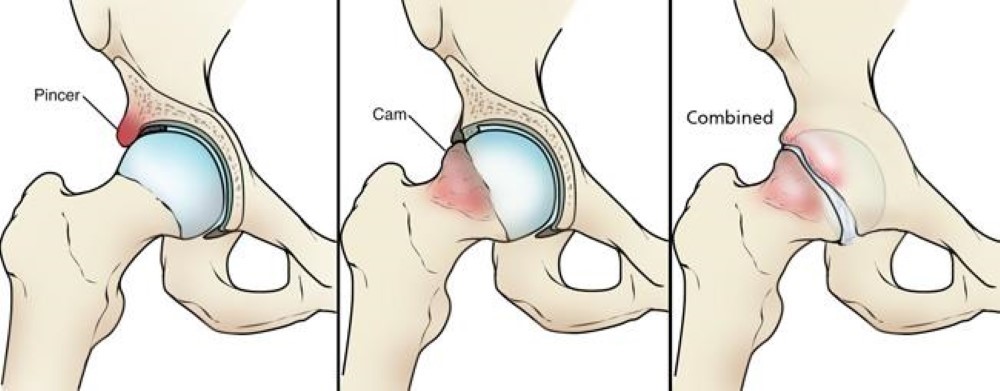

Outline the types of femoroacetabular impingement (FAI)